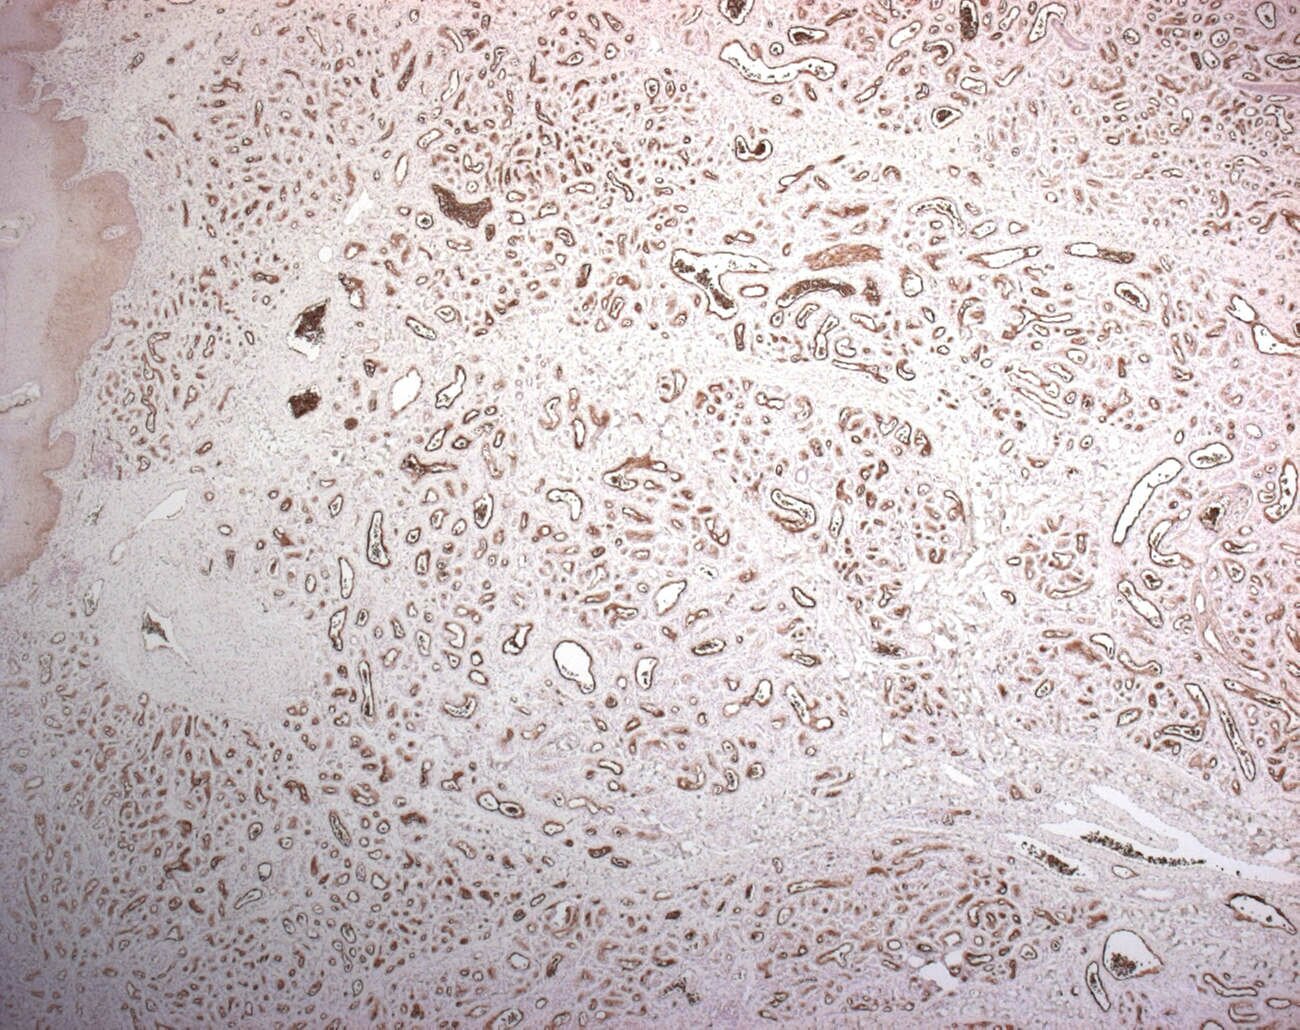

Immunochemsitry

WT1+

GLUT1+ (16230568)

| Tumors | GLUT1 | WT1 |

| infantile hemangioma | + | + |

| vascular malformation | - | - |